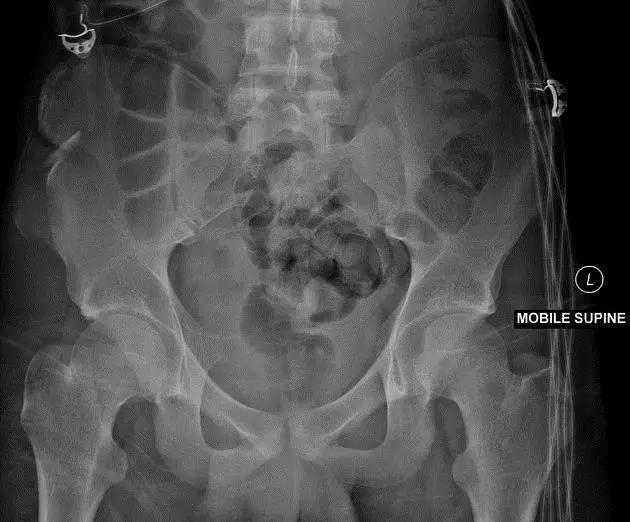

2. Malgaigne 骨折 (bucket handle 骨折,即桶柄骨折)

不稳定性骨盆骨折伴有前方和后方的骨折线累及髋关节。

(来源:radiopaedia)

3. Straddle 骨折

双侧耻骨上下支骨折。

(来源:learning radiology)